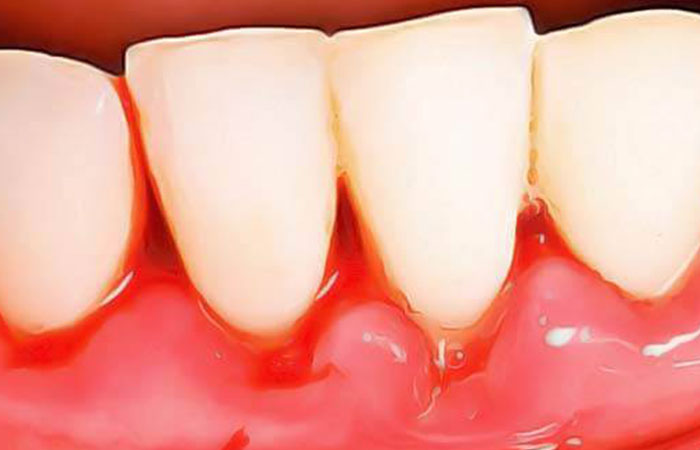

Maladies gingivales